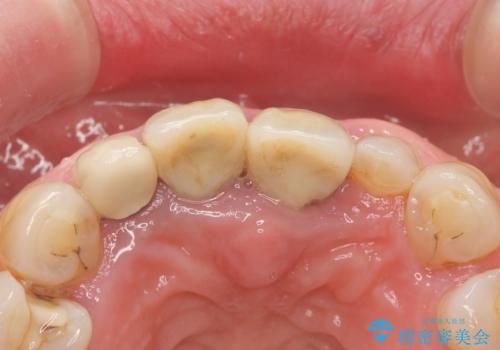

- 上下の前歯が抜けそうだとのことで来院されました。

精査したところ、動揺の著しい上下の前歯は重度の歯周病により保存不可能と判断しました。

ブリッジ、インプラント、義歯の選択肢の中で上下前歯ともにブリッジをご希望されました。